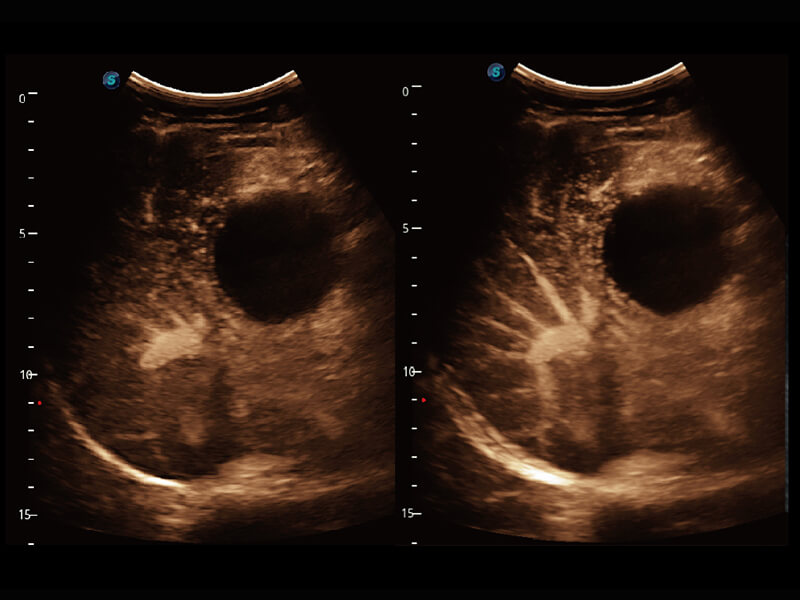

超宽频带技术,为容积成像带来优质的二维图像基础,为您呈现丰富的结构细节,栩栩如生地展示宝宝的宫内形态以及各种组织的立体结构。